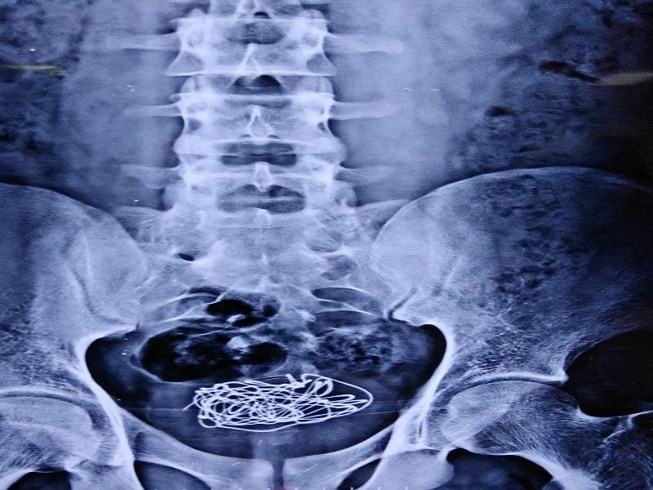

Nhét dây điện vào “của quý”, lọt đến tận bàng quang

Mới đây, một bệnh nhân người Anh phải nhập viện do bị đau nhiều ở bụng dưới, rát khi tiểu. Theo lời kể của cậu ta, 10 ngày trước cậu đã nhét một sợi dây điện vào niệu đạo, đây là ống trong dương vật thông với bàng quang, có nhiệm vụ lưu thông nước tiểu cùng tinh dịch. Đáng lo ngại là đây không phải lần đầu tiên cậu thực hiện việc này.

Các bác sĩ đã phải dùng laser cắt nhỏ sợi dây điện lọt vào bàng quang của bệnh nhân 18 tuổi. |

Mặc dù các bác sĩ đã cố gắng lấy sợi dây điện thông qua phẫu thuật nội soi bàng quang, nhưng sợi dây bị rối và quấn quanh bàng quang đến mức không thể di chuyển nó. Cuối cùng, bác sĩ phải sử dụng tia laser để cắt nhỏ sợi dây thành nhiều đoạn, sau đó gây mê cục bộ phẫu thuật lấy các mảnh dây này ra, đồng thời chèn vào bàng quang 1 vỏ bọc.